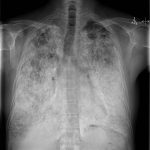

Vi Sỏi Phế Nang | Bài giảng CĐHA

Vi sỏi phế nang (Pulmonary alveolar microlithiasis – PAM) là bệnh hiếm gặp, đặc trưng bởi vô vố nốt ngấm vôi trong lòng phế nang. Bệnh gặp ở nhóm tuổi 4-9 ở Nhật và 30-50 ở phương Tây. Bệnh nguyên và bệnh sinh không rõ. Giả thuyết cho rằng do rối loạn chuyển hóa, phản ứng miễn dịch, bất thường về chuyển hóa calci, phospho…